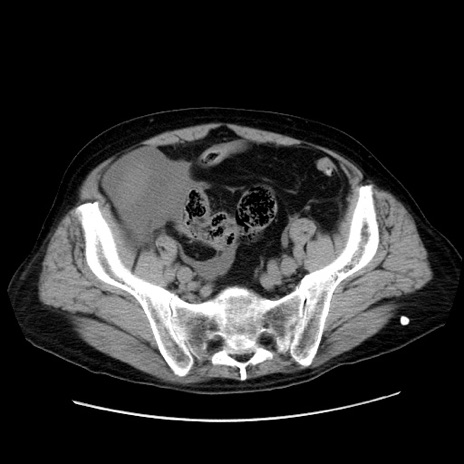

症例30(横断像)

【症例】80歳代男性

【主訴】臍周囲痛

【現病歴】約6時間前から臍下部痛が出現。次第に腹部膨隆・背部痛も生じてきたため来院。背部痛の場所は変化しない。

【身体所見】意識清明、BT 36.3℃、BP  131/87mmHg、P 87bpm、SpO2 100%(RA)、臍周囲自発痛・圧痛あり、反跳痛なし、自発痛部位に一致して板状硬あり、腹部膨隆、腸雑音減弱、CVA tenderness両側陰性。

【データ】WBC 19600、CRP 0.33